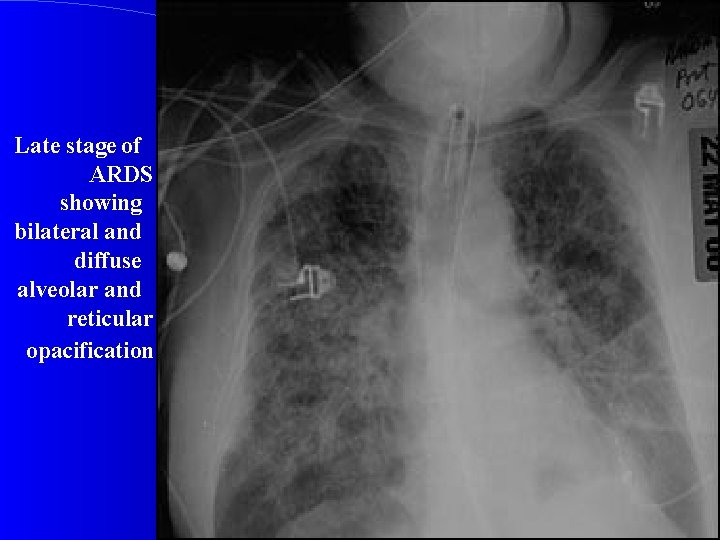

CXR Chest radiographic findings are non-specific and resemble those of typical pulmonary edema or pulmonary hemorrhage. There are diffuse bilateral coalescent opacities (the only radiological criterion defined by the Consensus Conference). The time course of ARDS may help in differentiating it from typical pulmonary edema. Chest x-ray features usually develop 12 -24 hours after initial lung insult as a result of proteinaceous interstitial edema. Within one week, alveolar pulmonary edema (hyaline membrane) occurs due to type 1 pneumocyte damage. In contrast to cardiogenic pulmonary edema, which clears in response to diuretic therapy, ARDS persists for days to weeks.

Late stage of ARDS showing bilateral and diffuse alveolar and reticular opacification